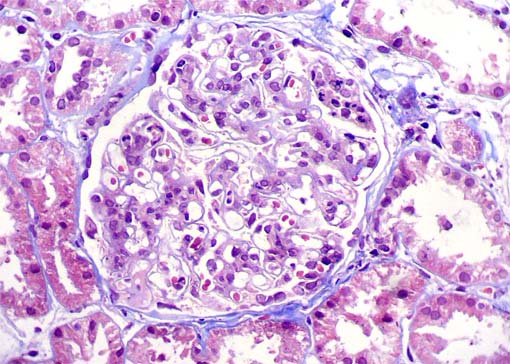

Figura 3.

H&E, X400.